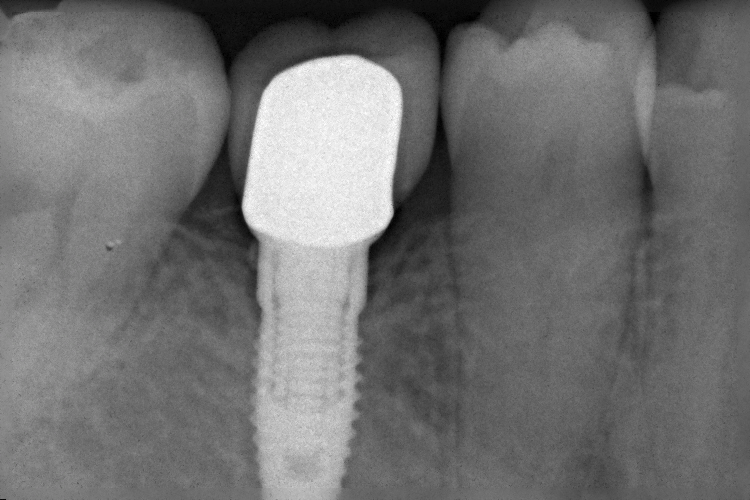

6番喪失後放置していたため7番が傾斜してしまいました

欠損部にインプラントを埋入します